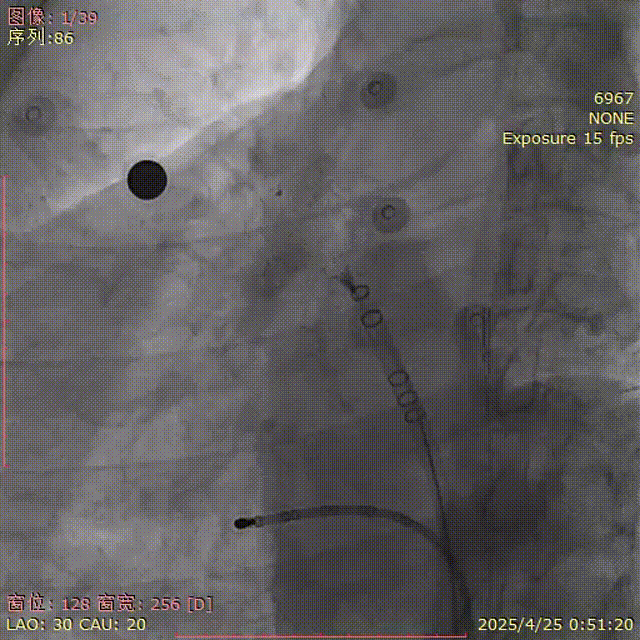

肩位造影

LAO 30° CRA 20°

肝位造影

LAO 30° CAU 20°

牵拉后再造影

肝位及纯足位下缘轻微露肩(少于封堵器尺寸1/3),肩位下无明显露肩,评估符合PASS原则

CAU 30°